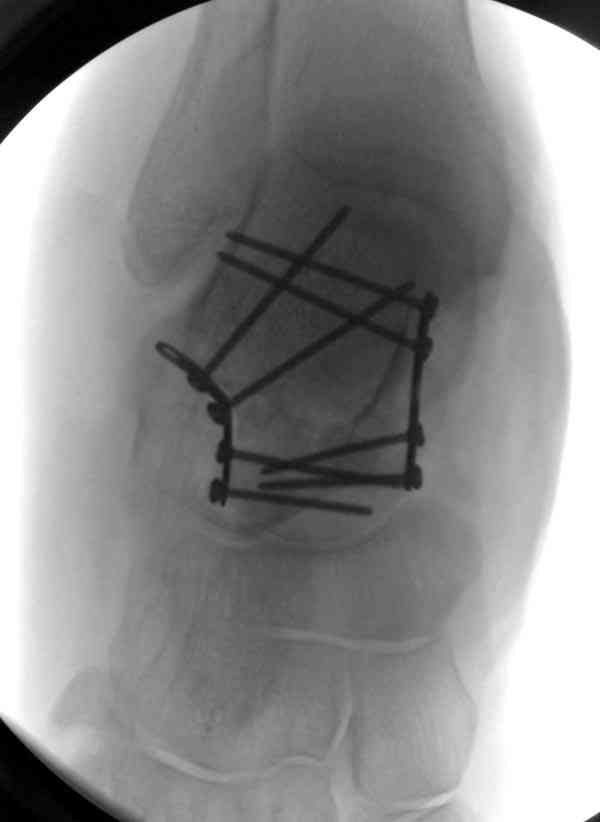

Случай с множественным оскольчатым переломом тарана оперированный из

двойного доступа.

Имя     : talar fx introp.jpg

Тип     : image/jpeg

Размер  : 19657 байтов

Описание: отсутствует

Url     : http://weborto.net:8080/pipermail/ortho/attachments/20070615/61a2112e/attachment-0014.jpg